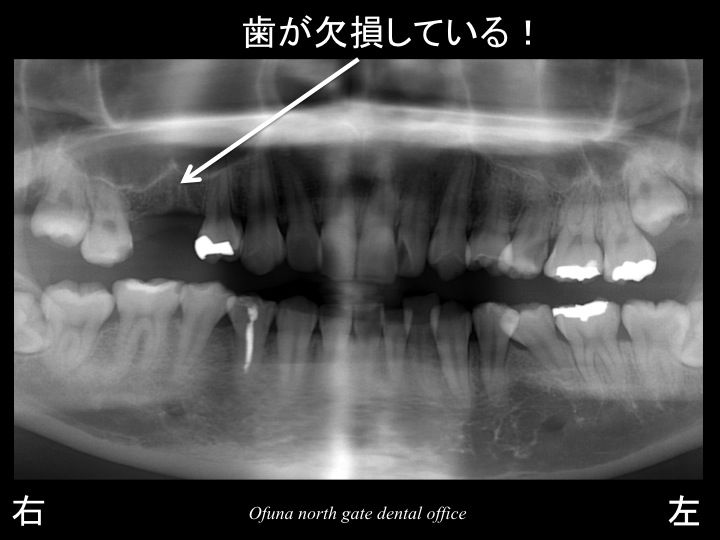

以下は初診時のレントゲンです。

上顎右側の奥から 3番目 と 4番目 の2歯分が欠損しています。